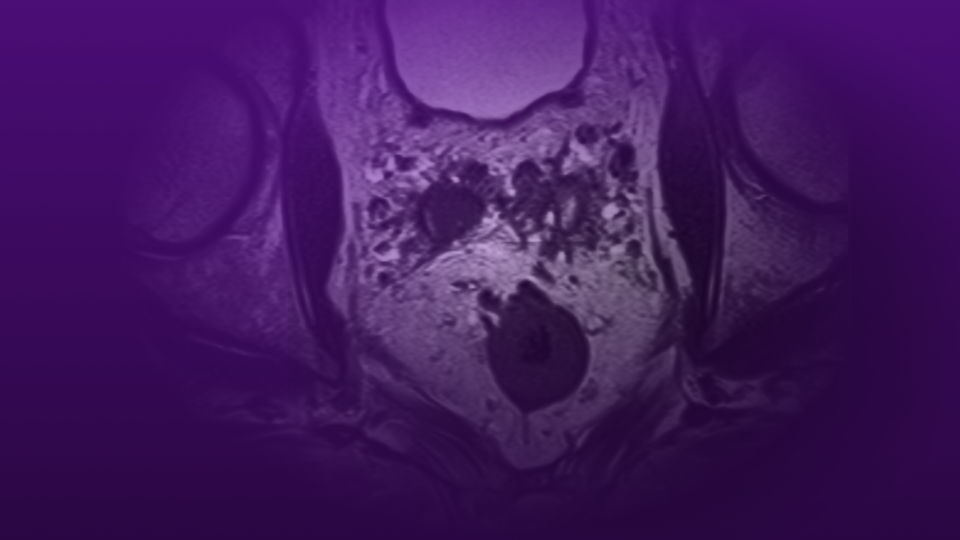

A diagram of the 3 main terminal branches of the pudendal nerve.

After a woman in her early 40s presented to NYU Langone with persistent stress urinary incontinence and vaginal pain, Dr. Rosenblum and Dr. Kirpekar ruled out causes such as interstitial cystitis, persistent genital arousal disorder, endometriosis, and a vaginal or urinary tract infection. Damage along the tri-branched pudendal nerve’s route through the pelvis can mimic many other conditions.